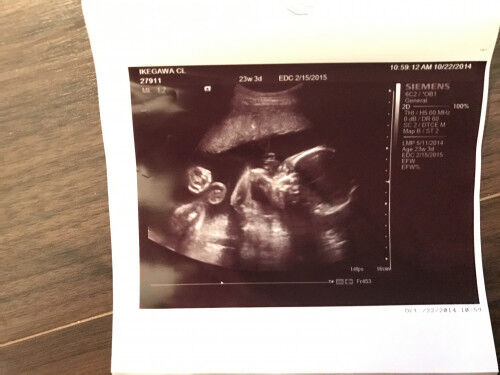

エコー写真で男の子・女の子の性別の見分け方をみていきましょう。 女の子の特徴 木の葉型・コーヒー豆がみえる 週数が経つと外性器が形成され、股の部分に割れ目がエコーで見えるでしょう。 女の子とわかった日。 テーマ: 3人目♡ 赤ちゃんの性別がわかった時に 書いてた記録です。 11月24日w2d 前回性別判定は見てくれなくて (次回ですね〜って言われた) もうwだしそろそろ分かるかな、、?エコー写真で男の子・女の子の性別の見分け方をみていきましょう。 女の子の特徴 木の葉型・コーヒー豆がみえる 女の子のエコー写真 16週の早期にはっきりと見えた、希少な例です! 週数別女の子のエコー写真 エコー写真の性別判断!

週数別女の子のエコー写真 ということで過信はしないにせよ、早速他の方のエコー写真を見てみましょう! 妊娠16週目の女の子のエコー写真 16週の早期にはっきりと見えた、希少な 女の子 エコー 葉っぱ 赤ちゃんの性別 すてきなママ 楽天ブログ エコー写真 これが葉っぱ いつもお世話になっております 30w時い女の子の性別判断 エコー写真です 先日7か月の定期検診で初めて性別を先生に聴きました。 男の子判定が女の子になるって、よくある事 妊娠コラム 妊娠で性別が女の子希望だったのに男の子だった。産まれてみたらどんな気持ち 妊娠・出産 胎児(お腹の赤ちゃん)の成長の経過|初期から臨月のエコー写真まとめ写真妊娠週0日(w0d)ごろの赤ちゃんのエコー写真です。投稿も募

妊娠24週でのエコー写真です 女の子でしょう とのことなのですが葉っぱ Yahoo 知恵袋